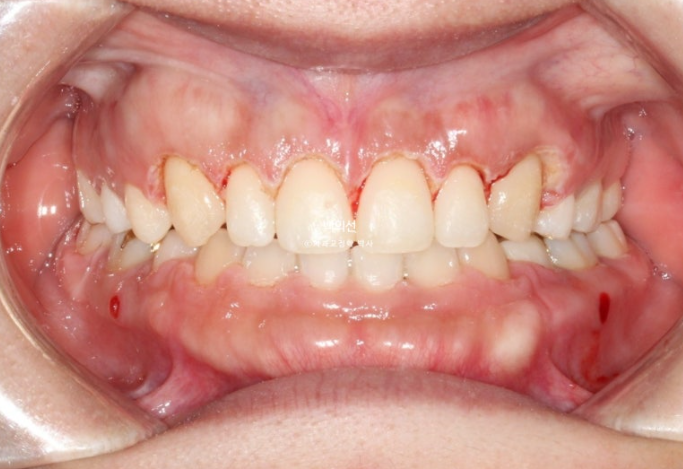

비대칭으로 인해 어긋났던 중심선이 맞아졌습니다.

교정만으로 턱뼈의 비대칭을 바꿀 순 없지만 최소한 치아중심선은 정확히 맞춰줄 수 있습니다.

교정 후 사진에서 앞니 교합이 다소 깊게 물리는 게 보이시죠?

의도한 부분이며 초진 시 앞니 물리는 게 얕으면, 재발을 고려하여 정상보다 좀 더 깊게 물리게 마무리 하는 게 좋습니다.

교정이 끝난 후 재발을 어느정도 고려한 과수정 즉 overcorrection의 개념은 치료에서 아주 중요하죠.